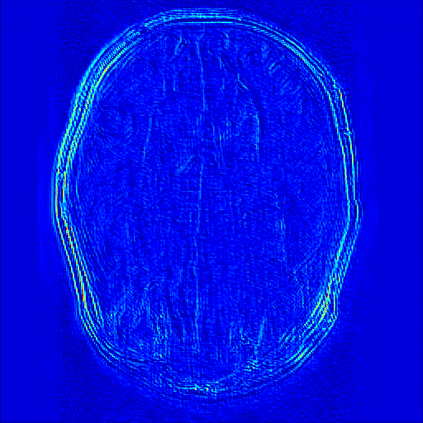

Reconstructing magnetic resonance (MR) images from undersampled data is a challenging problem due to various artifacts introduced by the under-sampling operation. Recent deep learning-based methods for MR image reconstruction usually leverage a generic auto-encoder architecture which captures low-level features at the initial layers and high?level features at the deeper layers. Such networks focus much on global features which may not be optimal to reconstruct the fully-sampled image. In this paper, we propose an Over-and-Under Complete Convolu?tional Recurrent Neural Network (OUCR), which consists of an overcomplete and an undercomplete Convolutional Recurrent Neural Network(CRNN). The overcomplete branch gives special attention in learning local structures by restraining the receptive field of the network. Combining it with the undercomplete branch leads to a network which focuses more on low-level features without losing out on the global structures. Extensive experiments on two datasets demonstrate that the proposed method achieves significant improvements over the compressed sensing and popular deep learning-based methods with less number of trainable parameters. Our code is available at https://github.com/guopengf/OUCR.